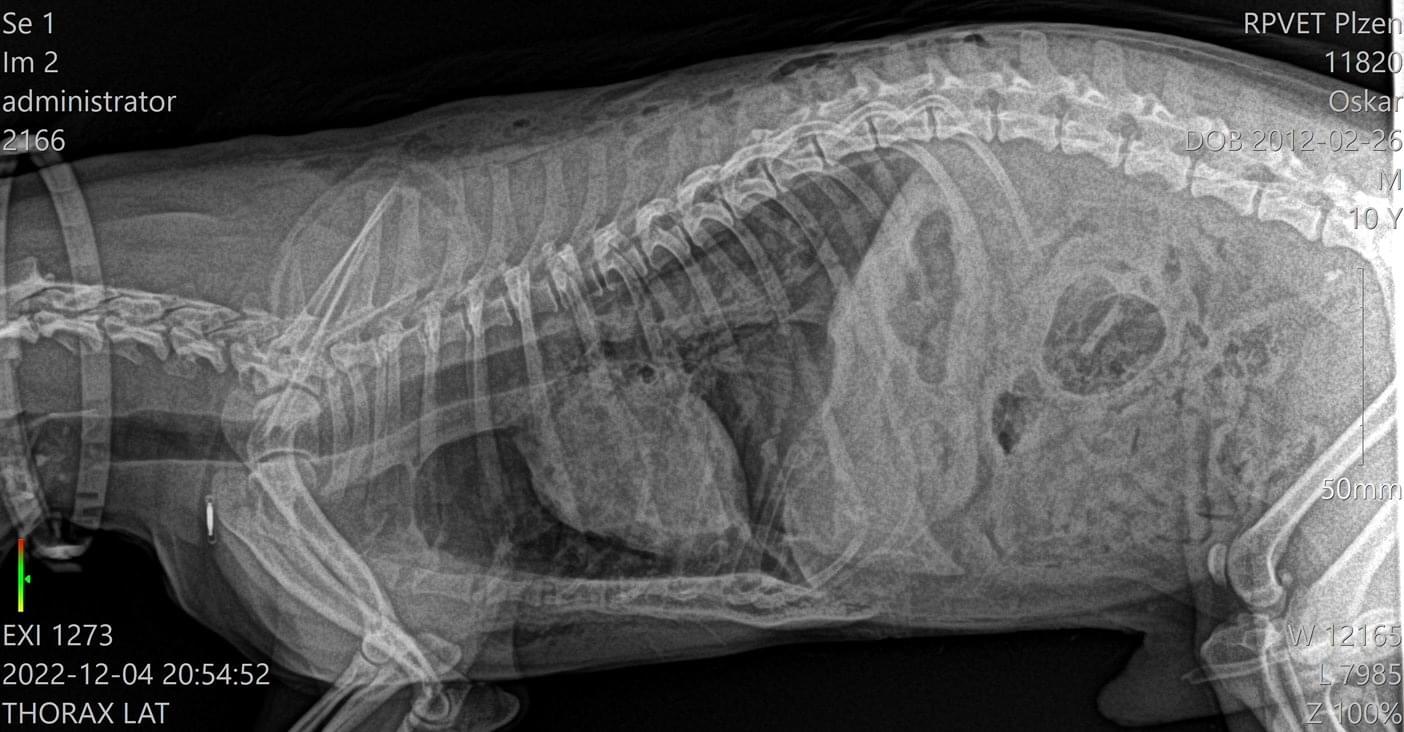

"Oskar ležel na zemi v krvi, takže jsme ho sebrali a hned jeli na veterinární pohotovost. Tam mu udělali RTG a jiná vyšetření, načež nám řekli, že má polámaná žebra a pneumothorax. Bylo nám oznámeno, že pokud přežije noc, udělá se chirurgický zákrok, ale po deseti minutách zemřel na kardiopulmonární selhání."